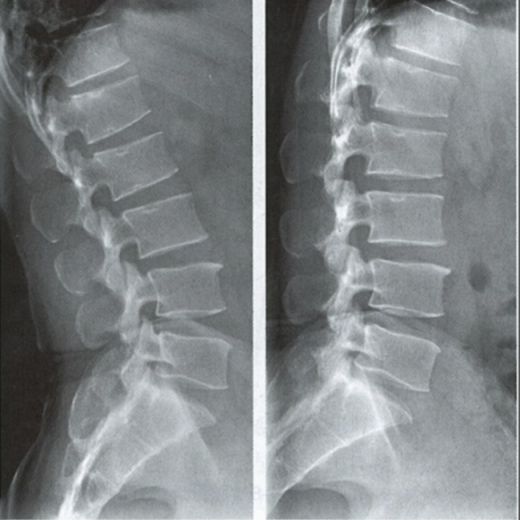

腰椎動(dòng)力位,也稱(chēng)為過(guò)屈過(guò)伸位,可以理解為兩個(gè)極限體位下的側(cè)位片,腰椎動(dòng)力位通過(guò)做最大程度彎腰(過(guò)屈)和后仰(過(guò)伸)的動(dòng)作拍攝側(cè)位片,來(lái)觀(guān)察腰椎在極限活動(dòng)下的表現(xiàn)。如果說(shuō)腰椎側(cè)位片能靜態(tài)體現(xiàn)椎體的解剖學(xué)結(jié)構(gòu)、序列及生理曲度改變,那么腰椎動(dòng)力位則是評(píng)估腰椎動(dòng)態(tài)功能性的檢查。

腰椎過(guò)伸位:是指腰部盡可能向后伸展,以雙髖關(guān)節(jié)位支撐點(diǎn),運(yùn)動(dòng)前后骨盆位置無(wú)改變。腰椎過(guò)伸時(shí),向前的曲度大于生理曲度,上部向后傾斜。

腰椎過(guò)屈位:是指腰部盡可能向前彎曲,以雙側(cè)髖關(guān)節(jié)位支撐點(diǎn),運(yùn)動(dòng)前后骨盆位置無(wú)改變。腰椎過(guò)屈的表現(xiàn)位向前的曲度減小、變直,上部向前傾斜。

當(dāng)1度及以上的滑脫時(shí)才可以在普通腰椎側(cè)位上觀(guān)察到,而1度以下的滑脫或失穩(wěn)則在普通側(cè)位片上難以發(fā)現(xiàn),這時(shí)候就需要借助腰椎動(dòng)力位進(jìn)行診斷。

腰椎動(dòng)力位 左圖為過(guò)伸位、右圖為過(guò)屈位